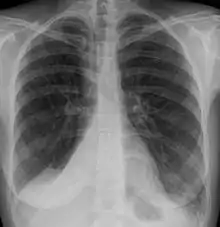

Clinically significant atelectasis is generally visible on chest X-ray; findings can include lung opacification and/or loss of lung volume. Post-surgical atelectasis will be bibasal in pattern. Chest CT or bronchoscopy may be necessary if the cause of atelectasis is not clinically apparent. Direct signs of atelectasis include displacement of interlobar fissures and mobile structures within the thorax, overinflation of the unaffected ipsilateral lobe or contralateral lung, and opacification of the collapsed lobe.In addition to clinically significant findings on chest X-rays, patients may present with indirect signs and symptoms such as elevation of the diaphragm, shifting of the trachea, heart and mediastinum; displacement of the hilus and shifting granulomas.[10]